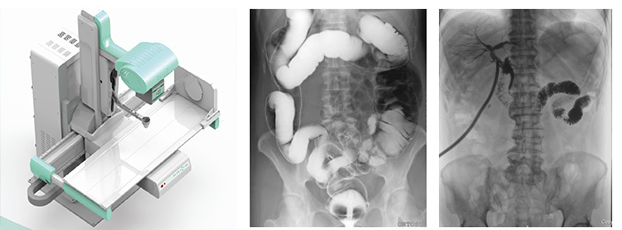

3、要擁有適宜床體高度的動態(tài)檢查床及全面的床體運(yùn)動功能,以輕松實(shí)現(xiàn)各種普通及特殊造影檢查,如食道造影、消化道造影、結(jié)腸雙對比造影、T管造影、靜脈腎盂造影(IVP)等。同時動態(tài)dr要支持醫(yī)生回放造影視頻,并可以抽幀,輔助疾病診斷。